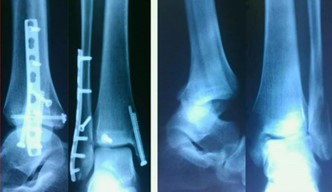

Открытый остеосинтез при переломе лодыжек — это хирургическая операция, при которой хирург через разрез обнажает костные отломки, сопоставляет их в правильном положении и фиксирует с помощью металлических конструкций, таких как пластины, винты или штифты.

Эта процедура необходима при сложных переломах, когда другие методы лечения неэффективны, и позволяет обеспечить надежное сращение кости.

Открытый остеосинтез при переломе лодыжек проводится для точного сопоставления и надежной фиксации костных отломков с помощью металлоконструкций (пластины, винты), что особенно необходимо при оскольчатых, смещенных или открытых переломах.